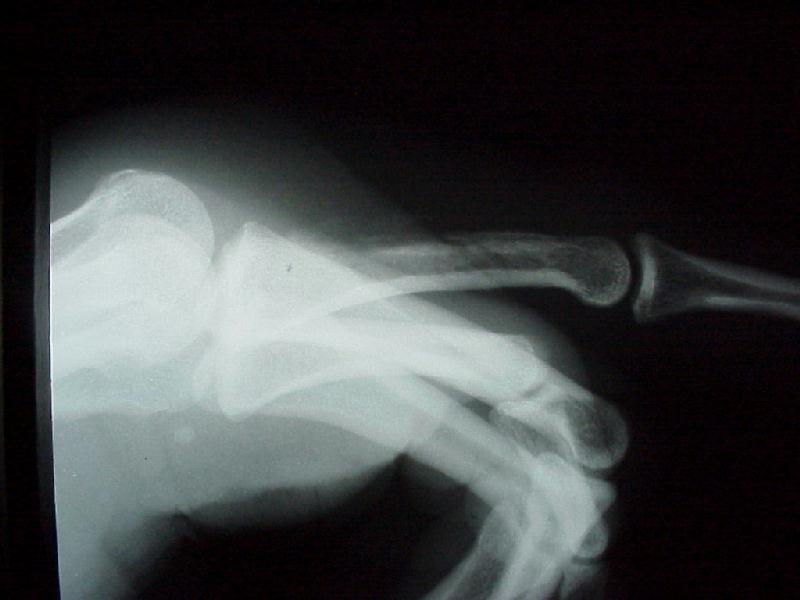

Clenched fist bite injury 12 hours old, rapidly progressive infection and divot in metacarpal head.